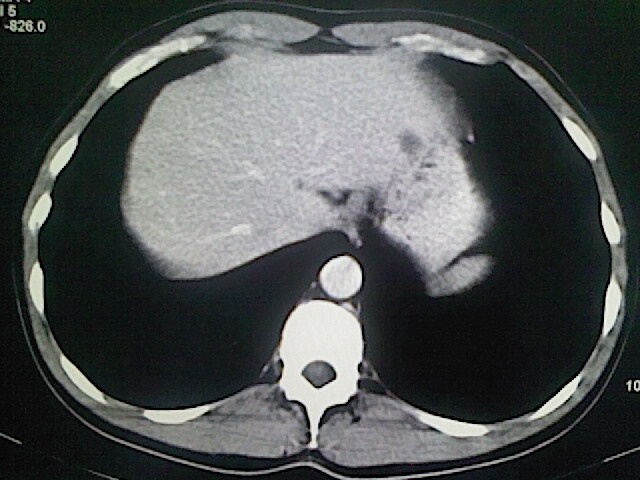

以下是引用卜一在2009-3-14 9:49:00的发言:[br]胆囊萎缩,胆囊壁不规则增厚,内部结构模糊,增强明显强化。另:肝左叶外侧段肝囊肿。支持:慢性胆囊炎!高度可疑:胆囊癌!

以下是引用余辉在2009-3-14 8:48:00的发言:[br]1)慢性胆囊炎。2)肝左叶外侧段肝囊肿。3)脂肪肝。[br]支持,胆囊萎缩,密度增高,不知b超具体有何提示,钙胆汁?结石?

以下是引用jiangjing在2009-3-14 10:18:00的发言:[br]1)慢性胆囊炎。2)肝左叶外侧段肝囊肿。3)脂肪肝。4.】建议行肝功能检查